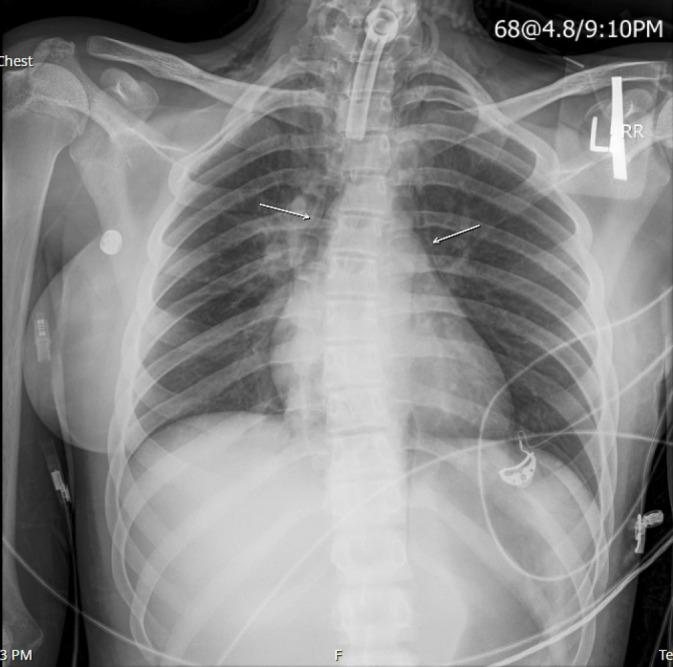

胸部X光在儿科患者气管切开置管中的应用价值。

Utility of chest x-ray for tracheostomy tube placement in pediatric patients.

To evaluate the utility of ordering chest x-rays after pediatric tracheostomy tube placement in identifying acute, post-operative complications and how it impacts clinical decision-making.

评估小儿气管切开术后进行胸部X光检查在识别急性术后并发症方面的效用,以及其如何影响临床决策。